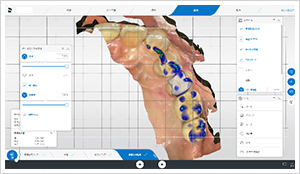

モニター上で、あらゆる角度から噛み合う部分や形を微調整して患者様固有の理想的な歯の形を設計します。

歯のデザインができたら、さまざまな色のセラミックブロックから最も適した色のものを選びます。